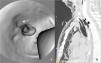

Iatrogenic tracheal rupture (ITR) is a serious complication secondary to procedures such as emergent orotracheal intubation or tracheostomy, among others. The management of ITR depends on the size, extension and location of the injury, along with the patient's respiratory status and comorbidities. The priority of treatment is to keep the airway permeable to ensure adequate ventilation. We present the case of a tracheal rupture after performing a percutaneous tracheostomy, in a patient diagnosed with severe acute respiratory distress syndrome secondary to bilateral interstitial pneumonia due to SARS-Cov-2. The issues are discussed, such as the management (conservative vs. surgical) depending on the features of the injury and the patient, in the extraordinary context that the COVID-19 pandemic has entailed.